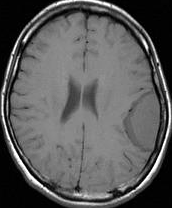

左は,造影剤を使ったガドリニウム増強MRIです。腫瘍が白く丸く見えます。右はフレア画像で,腫瘍の周囲の脳浮腫(脳のはれ)です。左前頭葉が,かなり強くはれています。この腫瘍は小さいのですが,脳のはれが強すぎるので手術摘出したほうがいいです。浮腫が悪化すると,てんかん発作や認知機能低下がでる可能性があります。

MRIでの髄膜腫の見え方は撮影の仕方によっていろいろです。左からT1強調画像,T2強調画像,フレア画像といいます。腫瘍の横に小さく白い領域がありますが,これは脳の腫れた部分で脳浮腫といいます。髄膜腫があると周囲に脳浮腫が生じることがあります。

最も見やすいのが,ガドリニウム造影剤を注射して撮影するものです。一般的に髄膜腫は造影剤で白く映し出されます。この腫瘍は左脳側にあります。MRIの軸面という輪切りの写真では左右が逆になりますから注意してください。脳を下から見た図になっています。MRIはいろいろな方向から腫瘍を見ることができますが,右は冠状断という正面から見た図です。よく見ると腫瘍の上と下のはじっこに線状に糸を引いたように造影される部分があります。これをテールサイン(しっぽのサイン)といいます。腫瘍が硬膜に沿って延びている可能性があることを示しています。